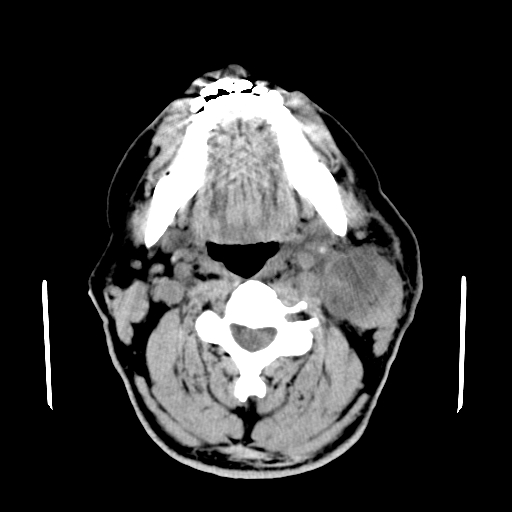

以下是引用卜一在2007-8-6 21:23:00的发言:[br]定位:左侧胸锁乳突肌内侧 颌下腺下后方。特征:弥漫性生长 软组织密度肿块,界限不清,内隐约见低密度坏死。考虑:神经源性肿瘤或血管源性肿瘤。

以下是引用wangzhanshuang在2007-8-6 21:08:00的发言:[br]腮腺混合瘤